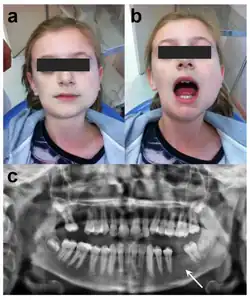

Facial swelling and infection due to Osteomyelitis of Tori

In the cases where osteomyelitis of tori occurs, treatment and management of this condition are adjusted. Instead of a scheduled oral surgery in regular cases where oral tori begin to cause discomfort or symptoms, the patient with osteomyelitis of tori requires prompt medical attention; a patient with this condition must be given intravenous antibiotics and anti-inflammatory drugs, (in some cases) receive a biopsy of the suspected or infected area, and receive surgery and management from an oral and maxillofacial surgeon. This is because osteomyelitis is an inflammatory process of bone and bone marrow which is caused by an infectious organism(s) which result in local bone destruction. These infections can vary from acute to chronic, with acute conditions being sudden and severe and chronic developing slowly and persistently.[14][15]